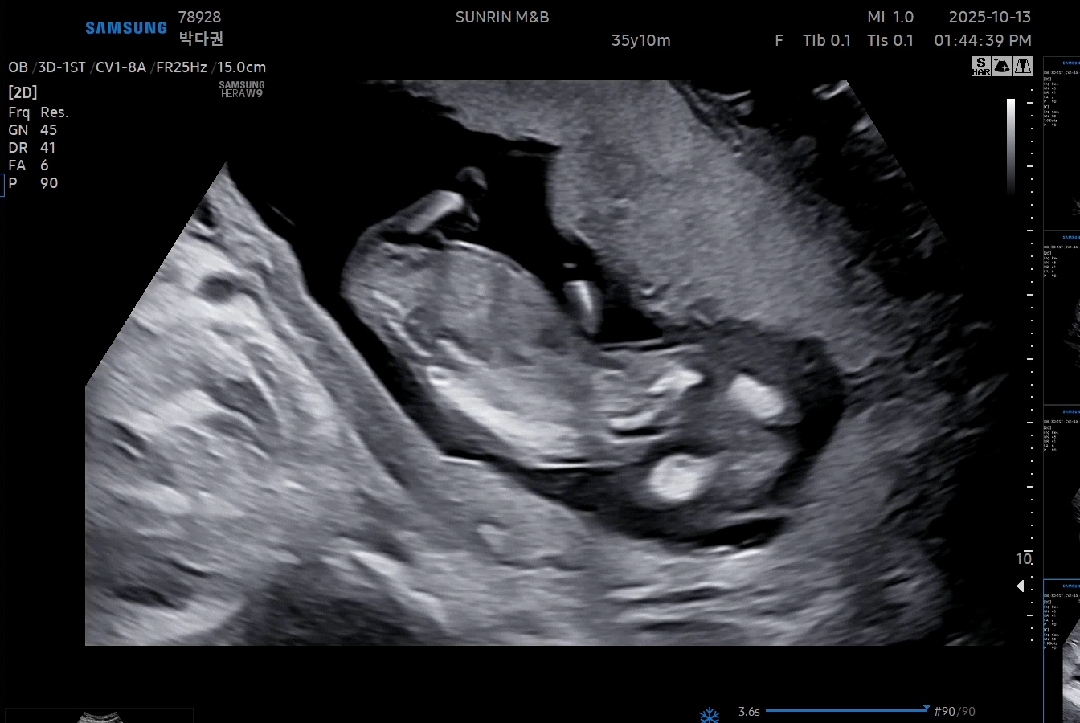

13주1일 성별같이 알아봐주세용😃

저희 애기 의사쌤이 보기엔 딸같다고하시는데 전 아들태몽을꿔서 아들인가 했늨데 아직 확실하진않다구하네여 남자애기일까요 딸일까요?